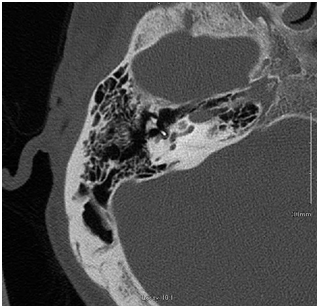

He was advised of the potential etiologies for sudden SNHL. Although the favored mechanism of loss was the result of a forceful and sudden lateralization of the stapes prosthesis, resulting in a PLF, surgical intervention was not encouraged given the duration of the deafness and the spontaneous resolution of the dizziness. Other etiologies were also considered. Therefore he did begin a course of high dose oral prednisone. A high resolution Temporal bone CT scan was obtained. Representative images are shown Figures 2 & 3. While not definitive, these did appear to show lateral displacement of the stapes piston. He returned to the office 1week later with no improvement in his hearing. The steroids were discontinued. His dizziness continued to resolve.

Figure 2 Axial Temporal bone CT. This image depicts the medial-most position of the prosthesis in the axial plane.